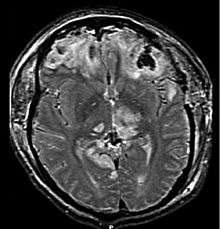

Acquired brain injury (ABI) is brain damage caused by events after birth, rather than as part of a genetic or congenital disorder such as fetal alcohol syndrome, perinatal illness or perinatal hypoxia.[1] ABI can result in cognitive, physical, emotional, or behavioural impairments that lead to permanent or temporary changes in functioning.[1] These impairments result from either traumatic brain injury (e.g. physical trauma due to accidents, assaults, neurosurgery, head injury etc.) or nontraumatic injury derived from either an internal or external source (e.g. stroke, brain tumours, infection, poisoning, hypoxia, ischemia, encephalopathy or substance abuse).[1] ABI does not include damage to the brain resulting from neurodegenerative disorders.[1]